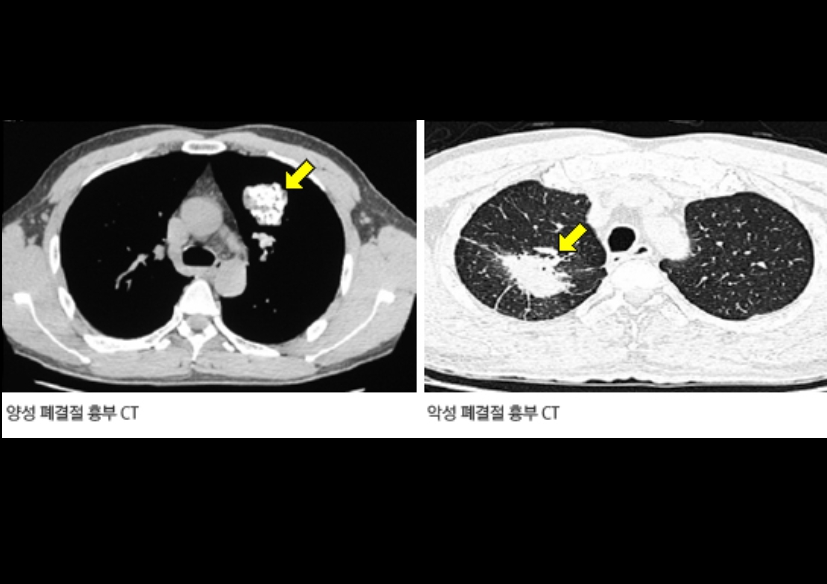

흉부 엑스레이 결절음영

결절음영이란 말은 엑스레이에서 ‘혹처럼 보이는 부분’을 뜻해요. 작게 하얗게 보이는 점, 혹은 둥근 모양의 그림자가 결절음영입니다. 이게 보이면 대부분은 오래된 염증, 흉터, 석회화(염증이 낫고 남은 흔적)일 때가 많아요.

하지만 간혹 크기가 크거나 모양이 울퉁불퉁한 경우엔 폐암 같은 질환을 의심하기도 합니다. 그래서 보통은 “추적 관찰”을 권해요. 6개월 또는 1년 뒤 다시 찍어서 변화가 없는지 보는 거죠. 제 지인 중 한 분도 건강검진에서 결절음영이 나와서 놀랐지만, 재검 때는 흔적만 남고 없어졌어요. 그때 이후로는 주기적으로 검사받는 걸 잊지 않으신다고 하더라구요.

Q3. 흉부 엑스레이에서 결절이 보인다고 하는데, 꼭 암인가요?

A. 대부분의 결절은 암이 아닙니다. 예전 감염의 흔적이나 석회화된 조직이 남은 경우가 훨씬 많아요. 하지만 결절의 크기나 모양, 가장자리 윤곽이 불규칙하다면 악성 가능성도 있으므로 정기적인 추적검사를 권합니다. 요즘은 저선량 CT로 더 정확하게 관찰할 수 있습니다.